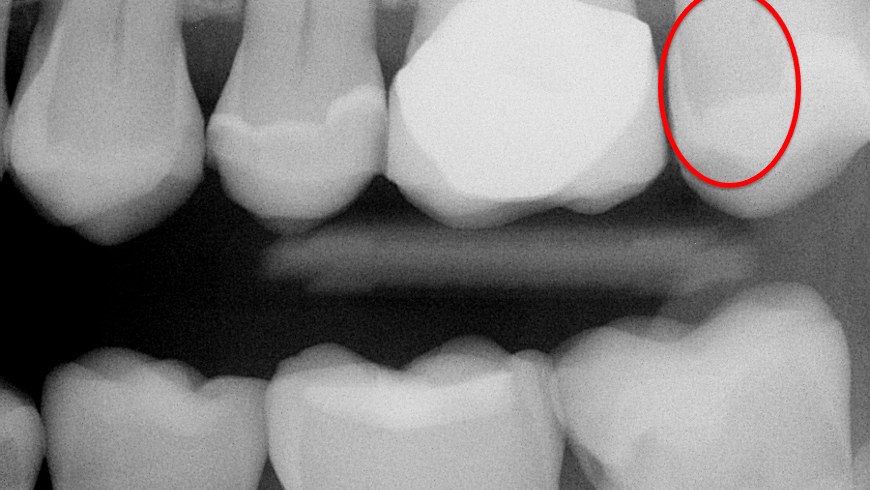

- Aren’t capable of showing initial or even deep dental caries (figures 1 and 2)

Lack of ability for current digital sensors to show initial dental caries. Clinicians have to wait too long before restoring teeth, which weakens the teeth, requires more time for the procedure, uses more material, and results in more difficult restorative procedures. Apparently, this problem cannot be overcome with the current generation of digital radiographs. Use of caries-detecting devices and careful magnified visual observation are the only current solutions.

Inconsistency of diagnostic data on images. Making images of a specific anatomic area often provides information that leads to different diagnoses of the same situation. Dentists admit that a definitive diagnosis often cannot be made because the radiographs differ in the digital images shown. Making more than one image of a specific suspicious location is one useful solution, but careful clinical visual observation with magnification is usually necessary.